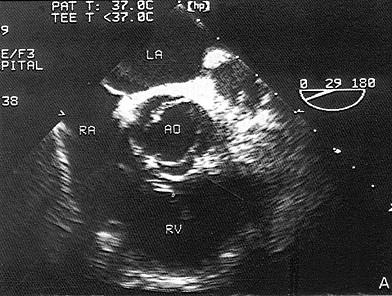

该病例最可能的诊断?(?)A.主动脉二叶瓣B.主动脉单瓣C.主动脉四叶瓣D.主动脉三叶瓣E.主动脉五叶瓣

问题 该病例最可能的诊断?(?)

选项 A.主动脉二叶瓣 B.主动脉单瓣 C.主动脉四叶瓣 D.主动脉三叶瓣 E.主动脉五叶瓣

答案 A